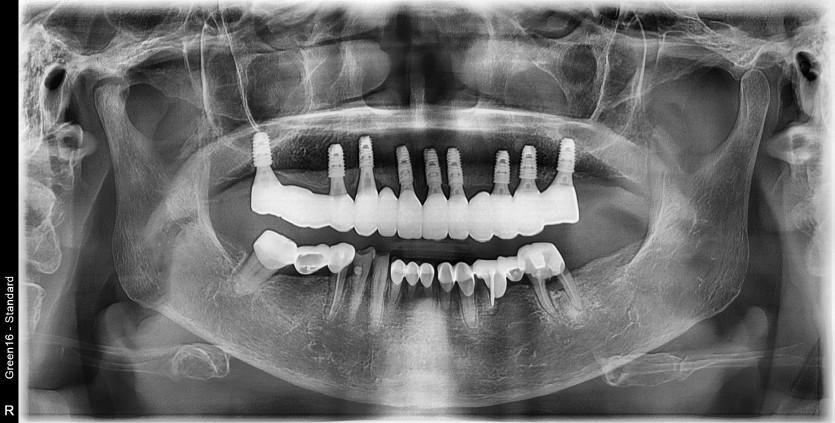

만 80세 상악 전체 임플란트 증례

상악 전체 임플란트 증례입니다.

9개의 임플란트로 완성하였습니다.